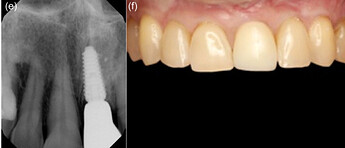

Minimally invasive removal of fractured central incisor and placement of immediate implant (Megagen Anyridge) without osteotomy on Patient 1: (a) Immediate prepless immediate implant on central incisor. (b) Anatomical healing abutment placed. (c) Transmucosal tunnel and emergence profile development by anatomical healing abutment. (d) Peri‐apical radiograph on the day of implant placement with anatomic healing abutment. (e) Peri‐apical radiograph with final restoration at 12 months. (f) Definitive monolithic Zr restoration.